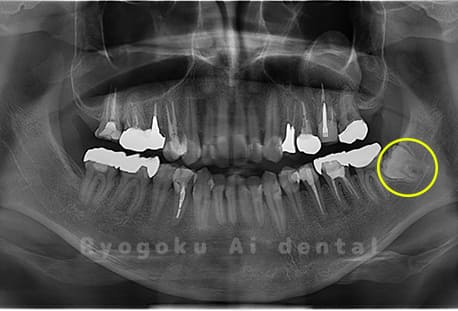

Case02

- 原因

- 下顎の水平埋伏智歯

- 治療内容

- 下顎の水平埋伏智歯を抜歯

<リスク・副作用>

手術後は痛み、腫れ、痺れなどの副作用が生じる場合があります。